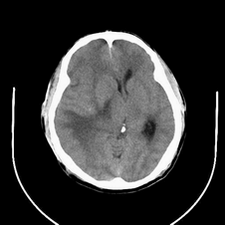

标题: CT25808:男,48岁,头痛多年,近段时间头痛加重伴步态不稳 [打印本页]

标题: CT25808:男,48岁,头痛多年,近段时间头痛加重伴步态不稳

平扫:右颞顶叶病灶呈等低密度伴大面积水肿,脑室受压变形。增强:病灶显著强化。考虑淋巴瘤或黑色素瘤。

1)不排除黑色素瘤可能;建议行mri检查。2)大脑镰下疝。3)脑积水(梗阻性)。